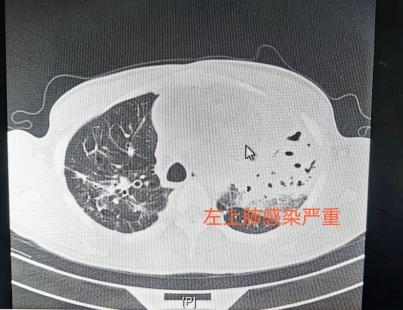

文先生的CT检查显示,他的前纵隔有个直径12cm的巨大占位。

纵隔占位考虑畸胎瘤,且肿瘤可能与左上肺的气管相通,一躺低即有少量囊液或肿瘤组织进入病人气道,造成剧咳。久而久之,造成左上肺严重感染,并通过气道影响到其他肺叶。通过多次送检,患者肺结核的指标均为阴性。针对原先抗真菌感染治疗效果不佳,专家也调整了抗感染方案。